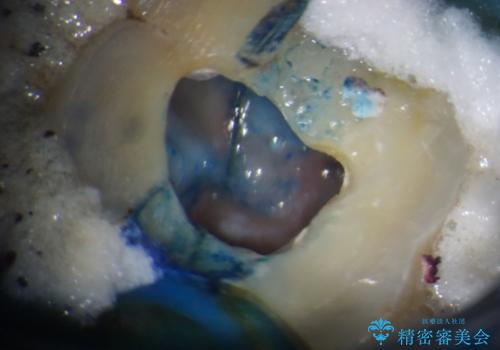

歯が割れているかどうかは、顕微鏡下で破折を確認することになりますが、割れていなかった場合には根管治療を行った上で補綴治療を行うことになるため、破折が確認できるまでは根管治療を行う前提で治療を進めて行くこととしました。

詰められた材料や壊死した組織を除去したところ、鮮明な破折線が認められたため、速やかに抜歯し、傷や骨の治癒を待って、サイナスリフトにより骨高さの低い部分にインプラント埋入を行いました。